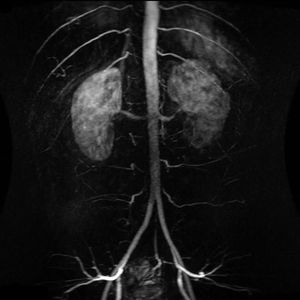

Shown here is a study called MRA with enhanced contrast of the abdominal aorta demonstrating normal paired arteries.What is MRA?Magnetic resonance angiography (MRA) is a group of techniques based on magnetic resonance imaging (MRI) to image blood vessels. Magnetic resonance angiography is used to generate images of arteries (and less commonly veins) in order to evaluate them for stenosis (abnormal narrowing), occlusions, aneurysms (vessel wall dilatations, at risk of rupture) or other abnormalities. MRA is often used to evaluate the arteries of the neck and brain, the thoracic and abdominal aorta, the renal arteries, and the legs (the latter exam is often referred to as a "run-off").